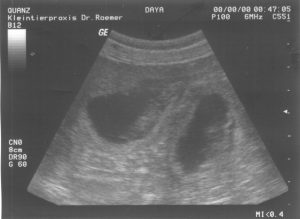

Heute waren wir zum Ultraschall bei der Tierärztin. Es waren mehrere Fruchthöhlen zu erkennen und wir konnten auch schon die kleinen Welpenherzen schlagen sehen. Was für ein spannender Moment !!